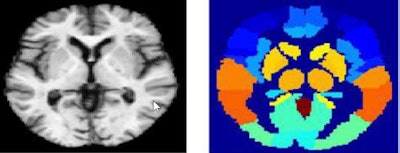

The team from the University of Malaga and the University of Granada developed multiple brain tissue classification methods based on deep learning and applied them to brain regions on MRI. The technique separates gray matter data from various brain regions into 3D patches, which are then used to train neural networks. The resulting classification method, validated on a large public dataset, showed classification accuracy of 95% for differentiating controls from Alzheimer's patients.

The classification methods based on deep-learning architectures are applied to brain regions defined by a technique called automated anatomical labeling (AAL). Gray matter images are divided into 3D patches according to the regions defined by the AAL, and then used to train deep belief networks (DBNs).